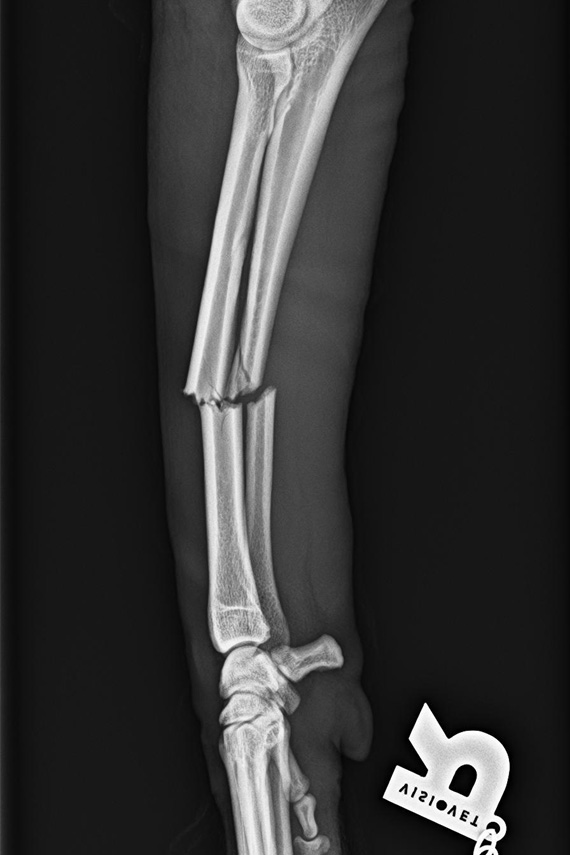

Trümmerfraktur bei einer Katze